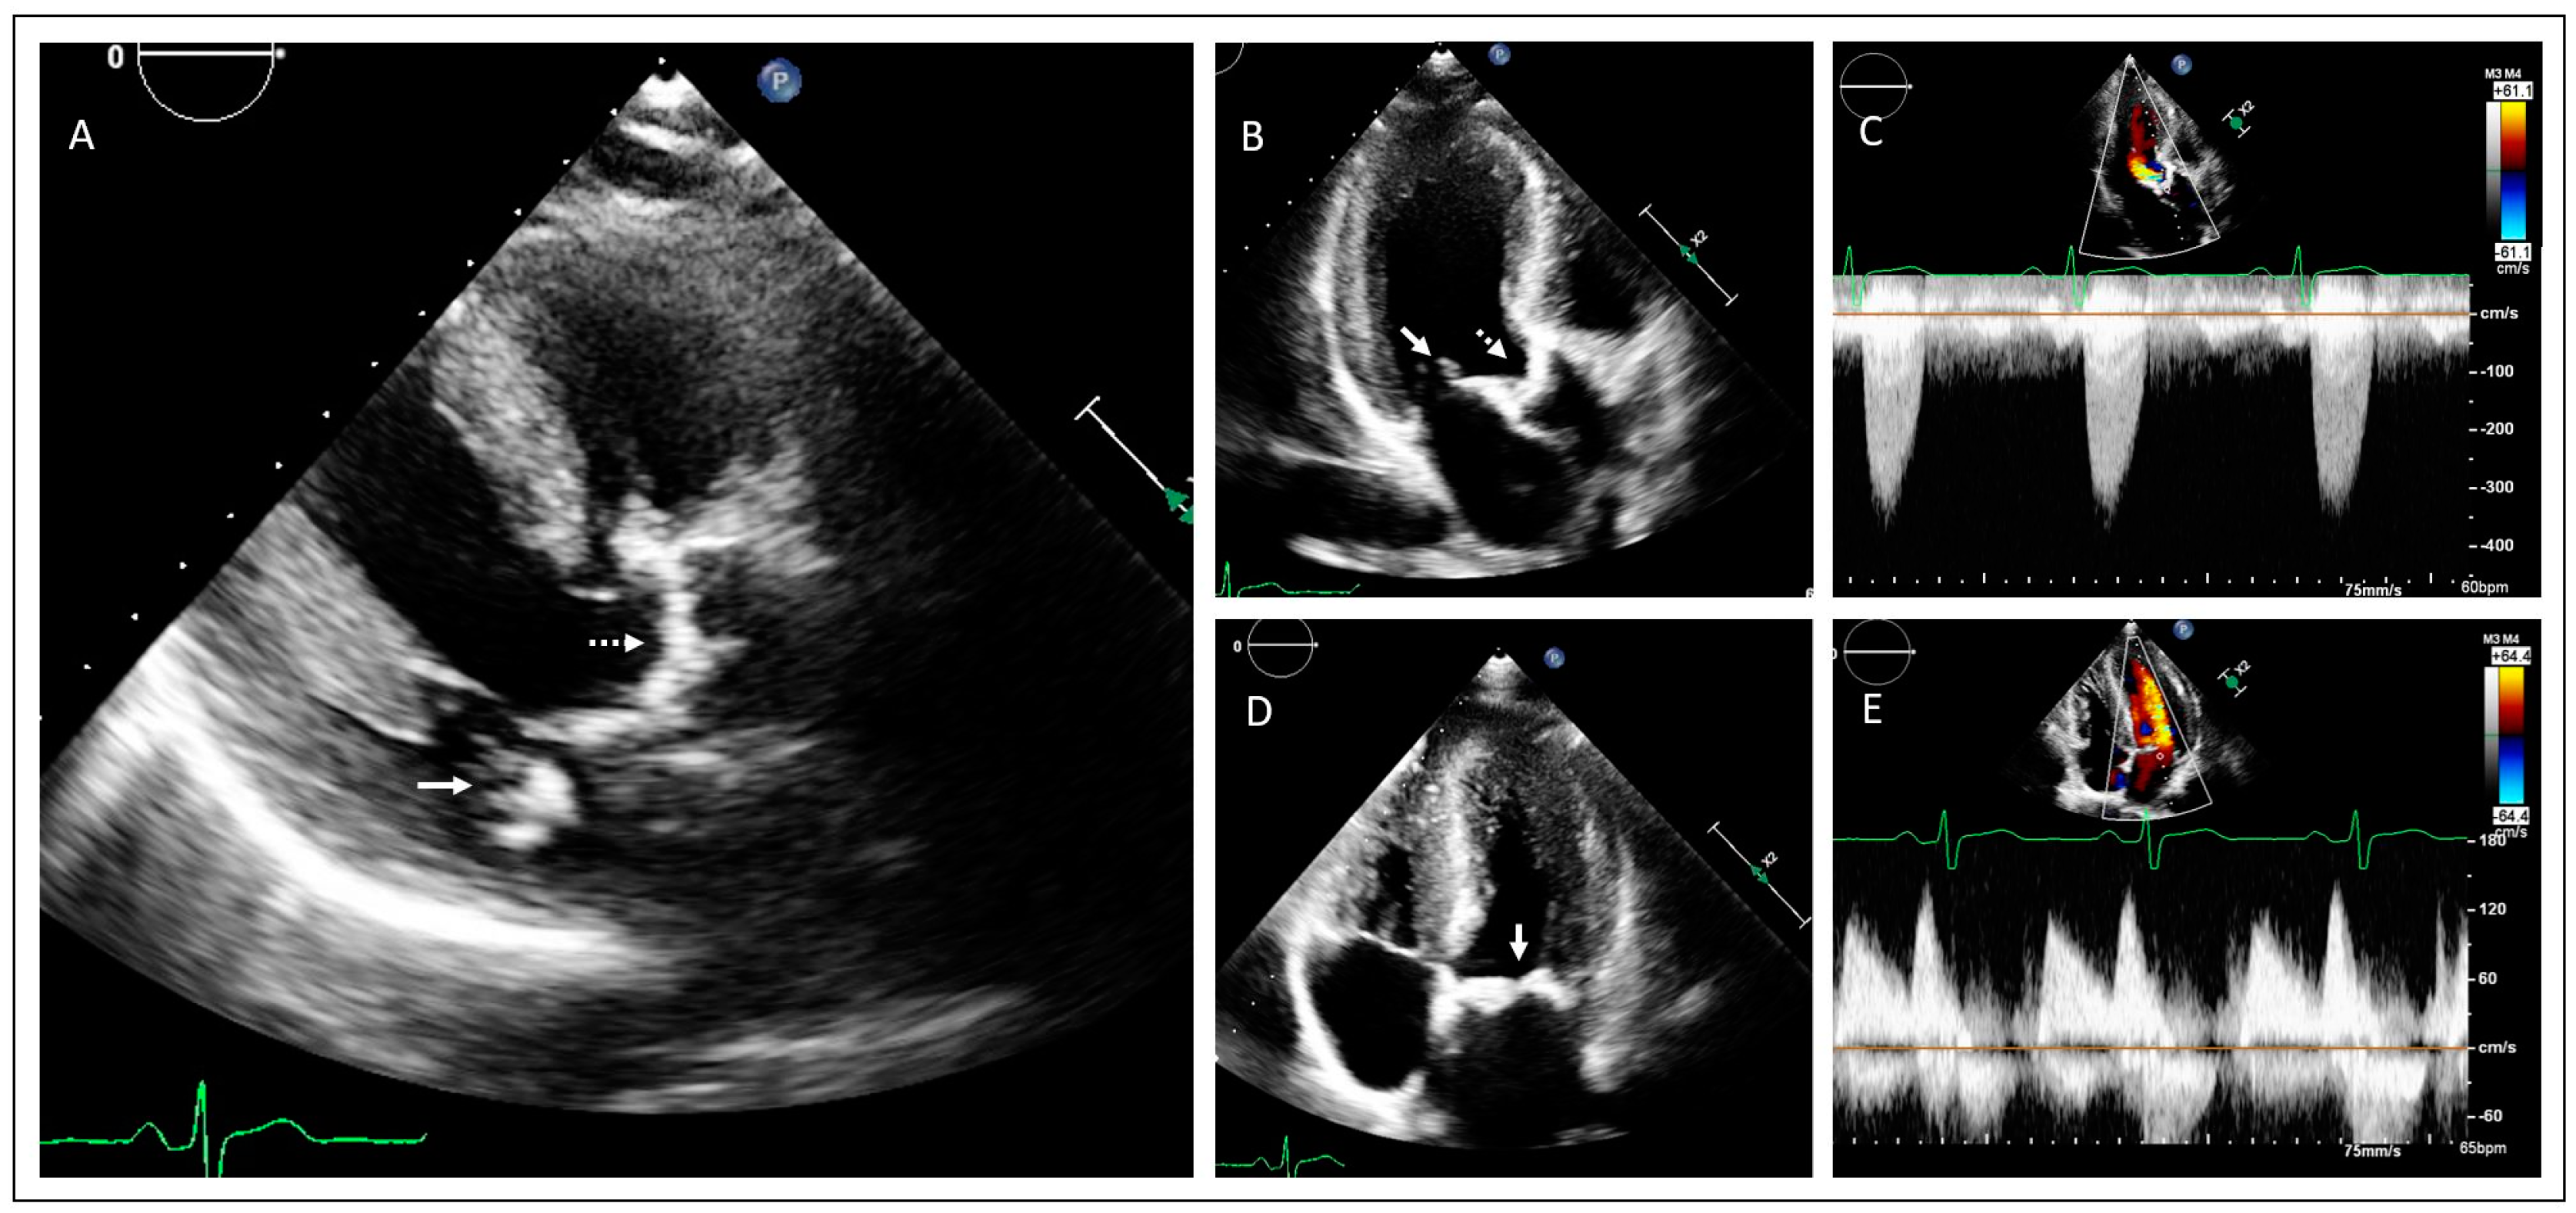

2. Case Presentations

2.1. Family 1

2.2. Family 2